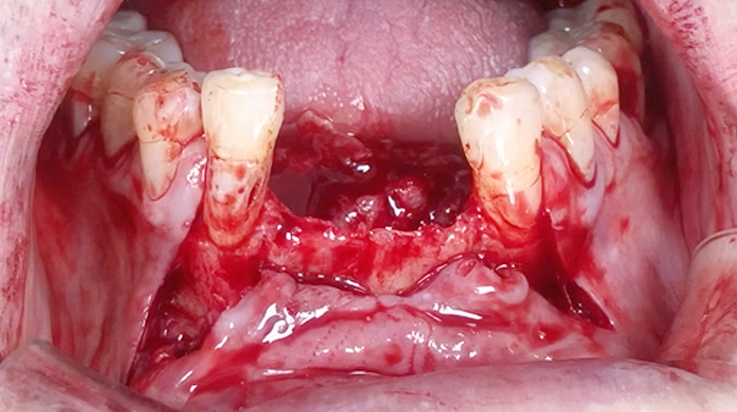

Horizontal ridge augmentation

A surgical procedure to increase the width of alveolar ridge which have been resorbed after tooth or teeth were lost